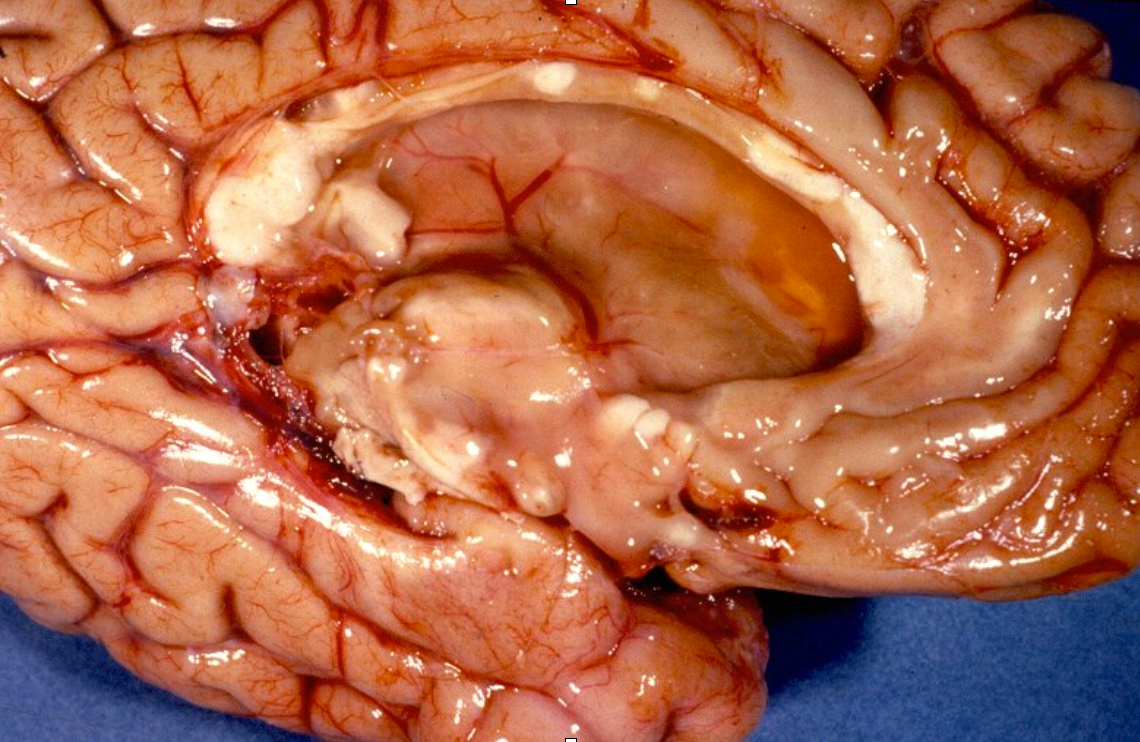

- Durante os trabalhos de dissecção de cadáveres foi descrito cicatrizes vistas como massas pálidas no tecido cerebral.

Exames de Imagem

incluir as imagens e as caracteristicas de em